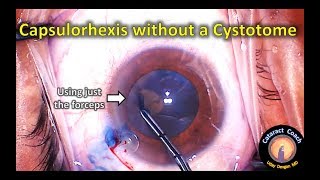

Continuous circular capsulorhhexis with a needle making the capsulorhexis without a cystotome during cataract surgery

making the capsulorhexis without a cystotome during cataract surgery Don't run your cystotome under the capsule!

Continuous circular capsulorhhexis with a needle making the capsulorhexis without a cystotome during cataract surgery

making the capsulorhexis without a cystotome during cataract surgery Don't run your cystotome under the capsule!